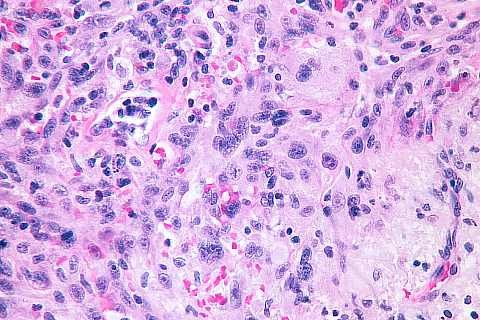

High power view within the main mass of the tumor: